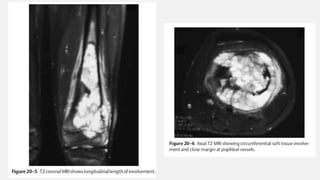

OSTEOSARCOMA DISTAL FEMUR

• A 10-year-old boy presents with a 3-month history of a painful left knee.

Before the onset of his pain, he was a fully functional youth, riding

horses and working on his parents’ ranch. He now presents in a

wheelchair with a painful, swollen left knee; examination is difficult

secondary to his extreme pain. Radiographic presentation includes plain

X-rays and a magnetic resonance image (MRI) of the knee.